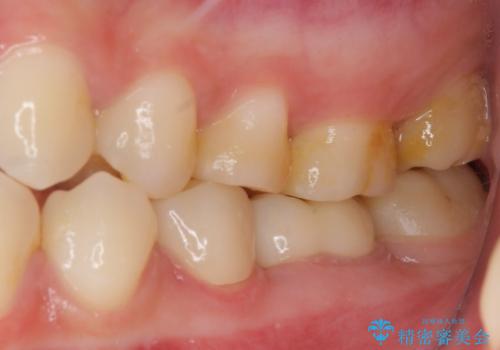

根歯の挺出(歯を引っ張り出す部分矯正)、歯周外科処置などを行った後、オールセラミッククラウンにて補綴することとしました。

当初は歯肉が腫れ上がり、大変不快な思いをされていましたが、セラミッククラウン装着後は清掃性が著しく改善し、患者様には大変満足していただきました。